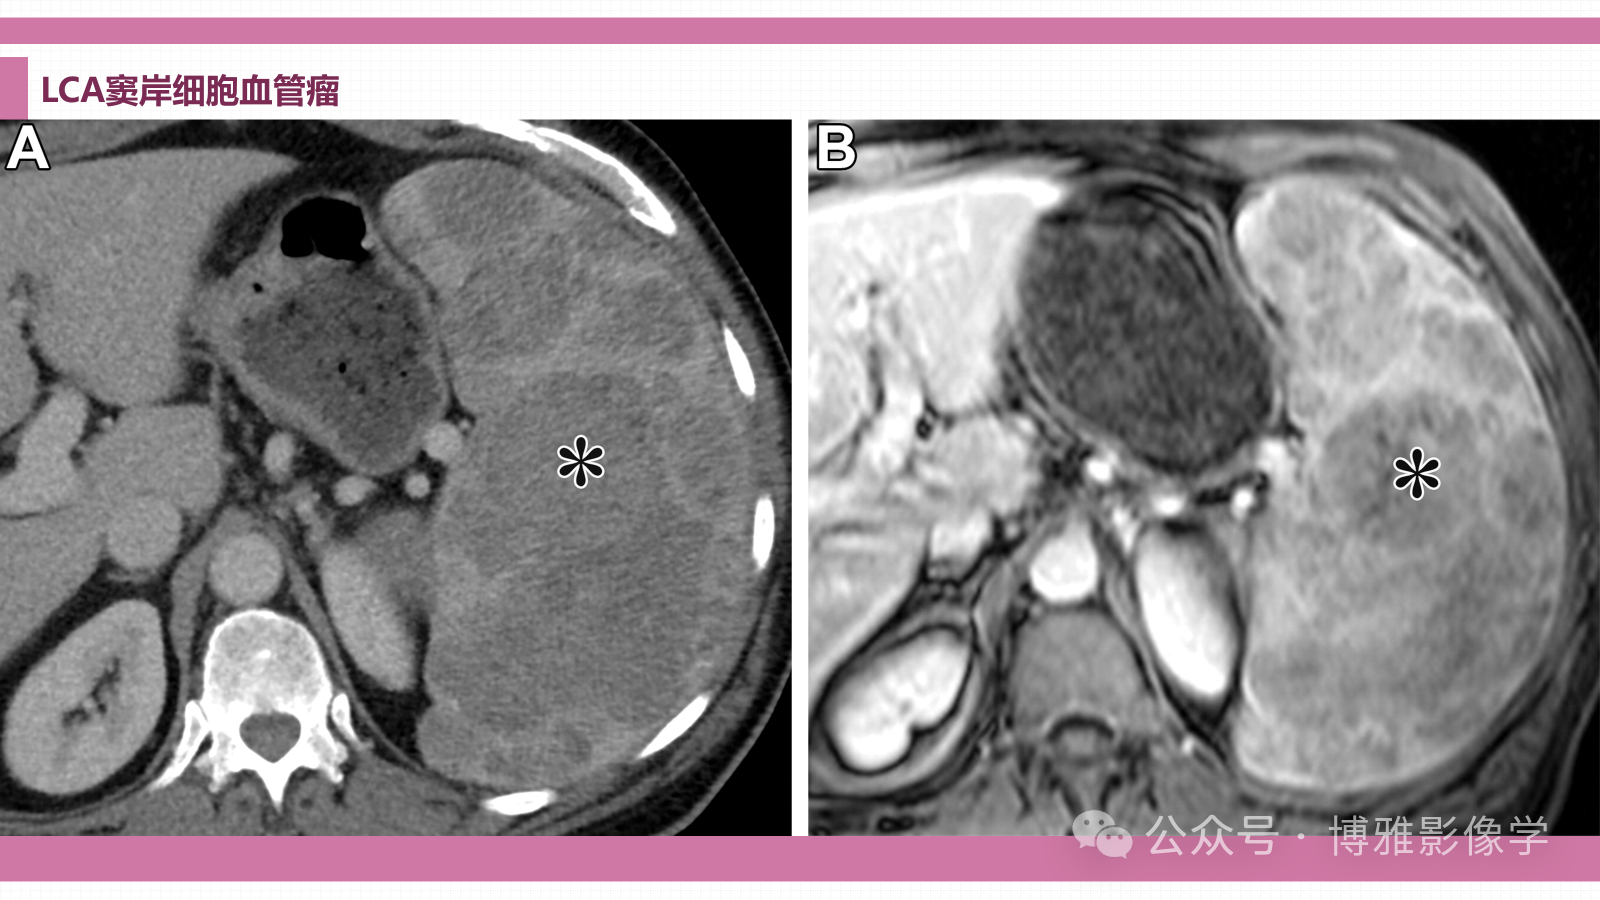

窦岸细胞血管瘤临床特征—LCA是一种良性血管肿瘤,被认为起源于脾窦内壁的窦岸细胞。LCA主要发生在没有性别偏好的成年人中,是良性的。大多数患者无症状,大多数肿瘤是偶然发现的。一些患者可能出现脾功能亢进的体征,包括脾肿大、血小板减少或贫血。病理特征—LCAs表现为多个海绵状和囊性结节,与背景脾实质轮廓分明,范围从红色到黑色(图E6)。在组织学上,LCAs边界不清,没有明确的包膜,由多个不规则的囊性血管通道组成,这些通道由饱满的立方形内皮细胞排列而成。血管通道可以具有不规则的管腔,具有进入血管空间的乳头状突起。血管间隙中可能存在大量从内层内皮分离的窦岸细胞和脱落的巨噬细胞。在免疫染色中,细胞对内皮标记物(CD31,因子VIII相关抗原)呈阳性,但对CD8始终呈阴性(不同于正常的窦岸细胞)。

影像学特征—LCA影像学表现是脾肿大,伴有许多进行性增强的结节。超声特征各不相同,包括无离散病变的弥漫性斑驳回声,以及多个低回声、等回声和高回声结节。在CT上,最常见表现是多个低密度病变,最初在早期和门静脉期弱强化,在延迟期上对背景脾脏的呈均匀等密度强化。MRI特征为持续T1低信号并伴进行性增强。T2影像学特征变化更大,信号增加(可能反映细胞性),信号降低(含铁血黄素)。

图15.患有慢性血小板减少症的65岁男性的LCA。门静脉期的增强CT(A)和T1(B)显示脾肿大伴多个低增强病变(*)。